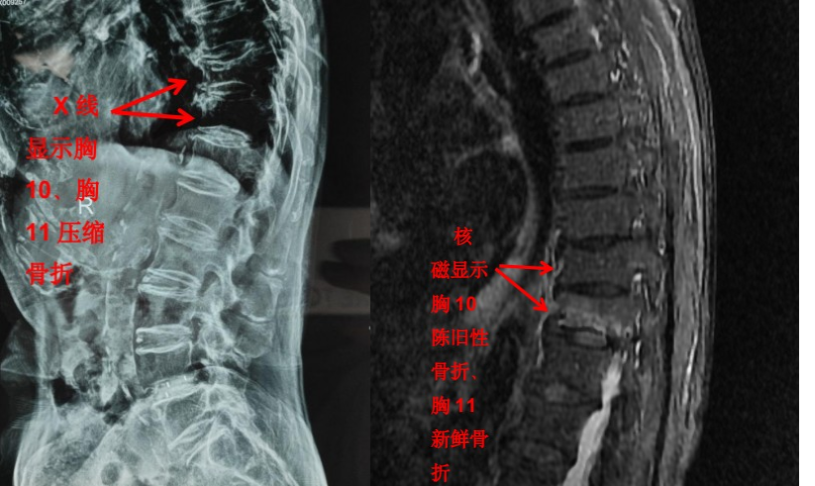

我们管 X 线检查叫 X 光片、照相或拍片。在 X 光片里,我们能看到脊柱有没有骨折,有没有骨质破坏,有没有脊柱侧弯、有没有骨质增生等。一些有经验的大夫,可以通过椎间隙高度的丢失判断椎间盘的退变程度。

但是对于大部分软组织病变如椎间盘、椎管内神经、有没有占位性病变等却无能为力。如果患者有压缩骨折,X 光片也无法判断是新鲜骨折还是陈旧骨折,这样也就无法定制下一步诊疗计划。

随着科技进步及医学的发展,核磁已经是脊柱外科不可或缺的检查手段。对脊柱、韧带、椎间盘、椎管内神经及椎旁组织显影都优于 CT,通过腰椎核磁我们可以直观地看到椎间盘突出的程度、神经受压的程度,以及压缩骨折的新鲜程度。